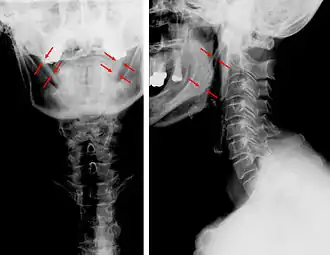

Radiographies du rachis cervical, face et profil. Aucune malposition ni aucun processus dégénératif n'est notable. Les corps vertébraux comme les structures annexes sont de structure normale. Cependant est notée une large calcification du ligament stylo-hyoïdien, à droite comme à gauche du cou. Les symptômes du patient pourraient être reliés au syndrome d'Eagle.

Symptômes Cervicalgie, otalgie et douleur de l'épaule (d)